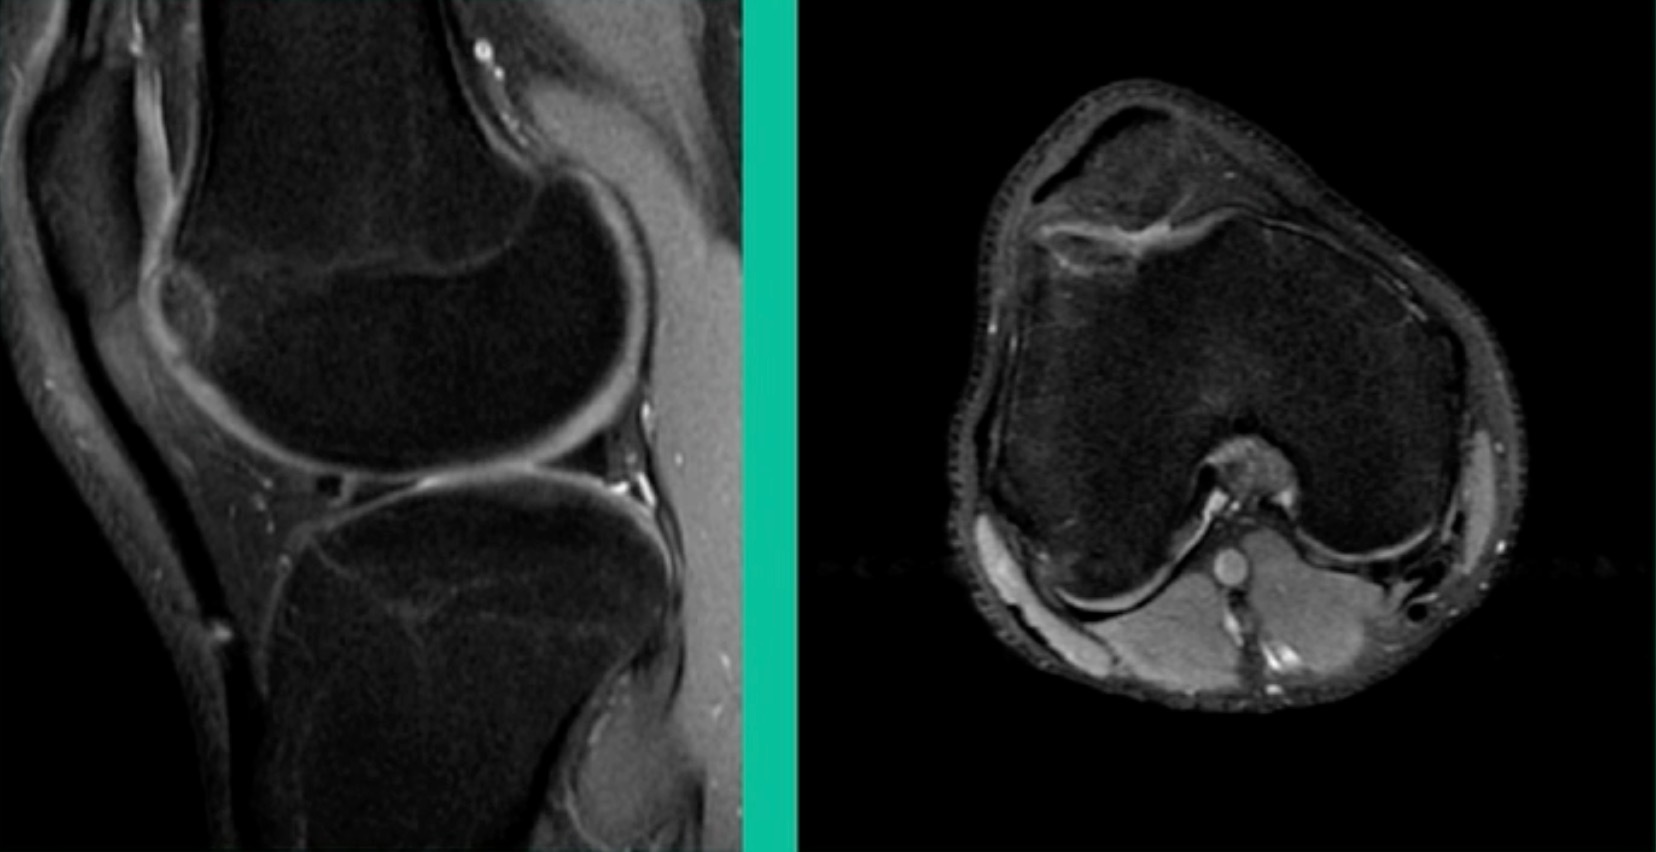

43-Year-Old, symptomatic medial femoral condyle.

D1 football player formally, affecting ADLs. For this one, I initially just wanted to watch it. This looks pretty small when he came in. Let’s see what happens. Six months later, this is where he progressed to.

We get in there, it’s delaminated, not much bone, nothing to fix in my mind, and so we drilled it.

How do these do? There’s actually reasonable data for marrow stimulation for OCD. But if you have the option for small defects, I would prefer an osteochondral allograft over microfracture based on the literature. That’s the take-home. Marrow stimulation, if you do it, you’re probably better off drilling it. We showed that we could reduce revision rates with marrow stimulation by two-thirds if you drill it versus use a microfracture awl.

Another one. 24-year-old right knee pain, ADL discomfort, normal alignment, lots of symptoms, thought I might be able to fix it.

I get in there, the pieces are just fragmented, I’m not going to fix it. This is the lateral aspect medial femoral condyle. Statistically, this one can do well. You take the piece out, they say, “I feel better.” It’s on the upslope of the lateral aspect medial femoral condyle. They feel fine, right? That’s not the case here. This one still continued to have symptoms.

So, what do we do for this one? This one got an osteochondral allograft.

I gave you a whole talk earlier on today about OA grafts. This is my mainstay for a salvage. I do not pull this out of the bag when the patient walks in the office for their first-line treatment. First, they get a scope. If it can’t be fixed, it comes out. If it can be fixed, we fix it with metal screws if it’s grossly unstable. If it’s not grossly unstable, we use biocomposite screws. If they get fixed, they go back to sports in four months. If they fail, they generally get this (Figure 28).

This is another one. 38-year-old, lateral side knee pain, lots of edema.

What’s amazing with this one is he’s got that little focal defect, but tremendous edema there and lots of bone pain. This one, we did something called AutoCart™ (Arthrex, Inc.).